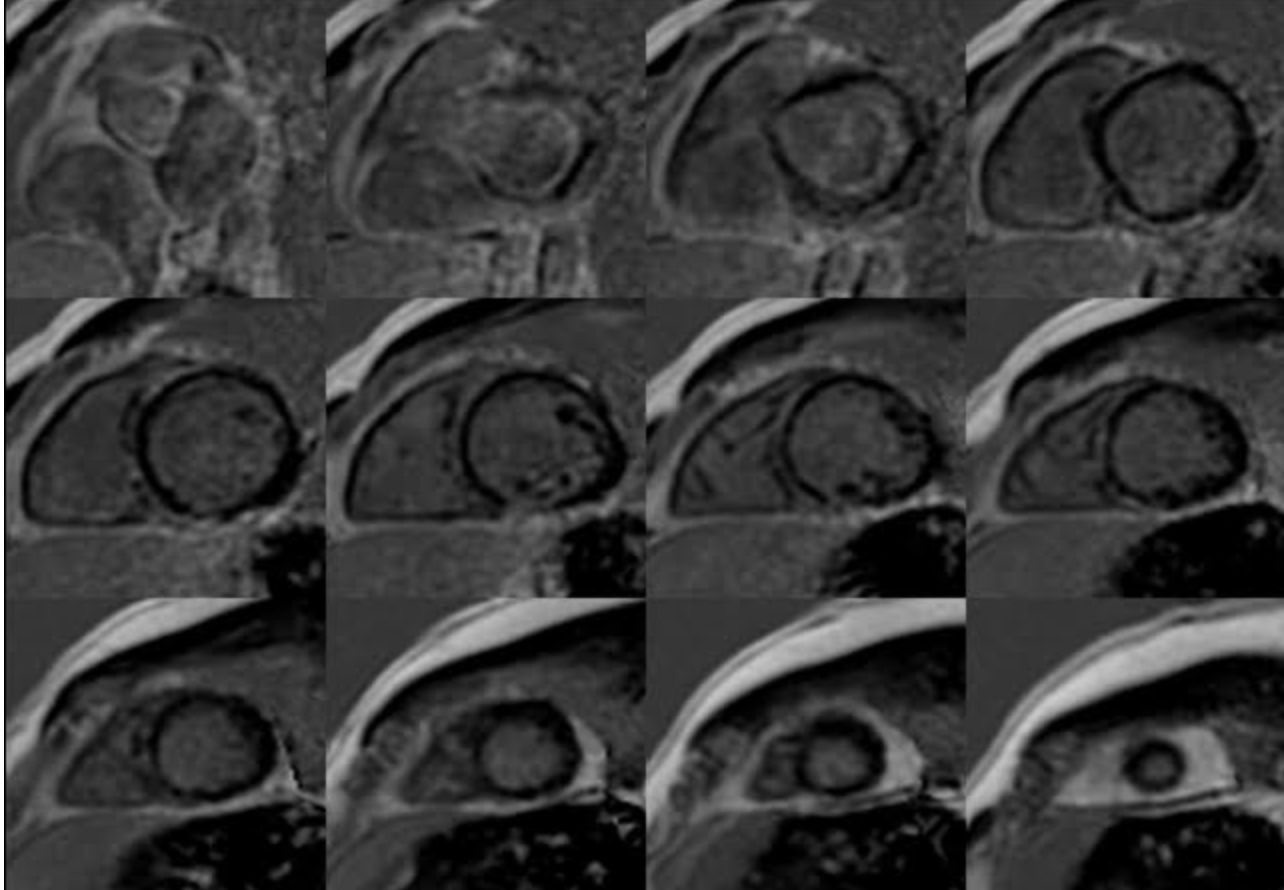

Figure 3. Short-axis LGE images demonstrating circumferential/ring-like late gadolinium enhancement in the left ventricular myocardium